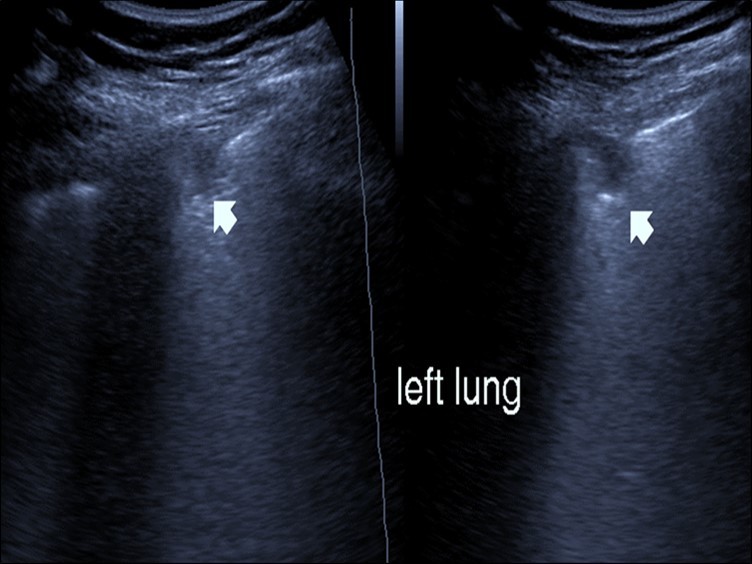

Bed side chest ultrasound may reveal positive findings as multiple Kerley’s B lines (>3 per intercostal space), pleural wall thickening (Figure 1), patchy areas of pulmonary consolidations especially in subpleural location (Figure 2, Figure 3) and obstructive lung collapse.

Figure 1.Real time chest ultrasound showing Kerley’s B lines in patient with covid -19.

Real time chest ultrasound showing Kerley’s B lines in patient with covid -19.